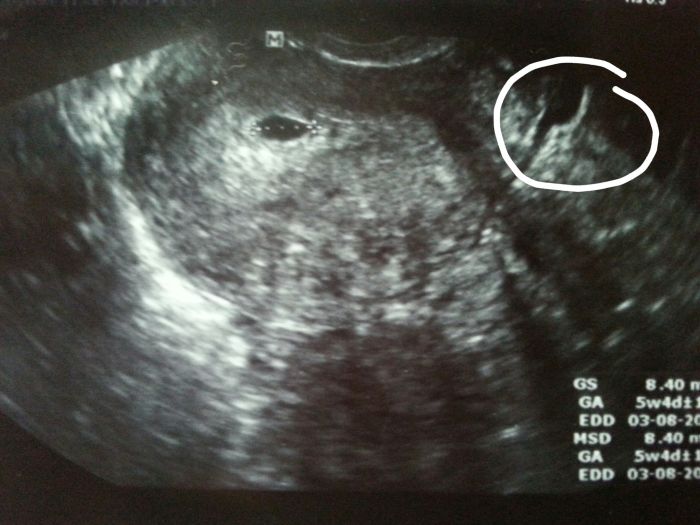

Ahojte holky. Nejak mi to neda ale musim se vas zeptat. Co vidite na UTZ? Nekdo mi totiz rika ze vidi jeste jeden ten vacek na prave strane, nekdo zase ze je to mimodelozni na te prave strane. Co si myslite vy? To na levo je kde ma tudiz v deloze :-D ale to na pravo? Lekar si toho nevsiml -_-

[675044]Very na pravo už nevidim nic... :O

[675118] toto kazdy mysli. Ja sama jsem z dvojcat tak me budti desi a nebo mam smulu :D

To už je moc daleko ne? Nemůže to být jen stín?? Pochybuju, že by to dr. přehlídnul...